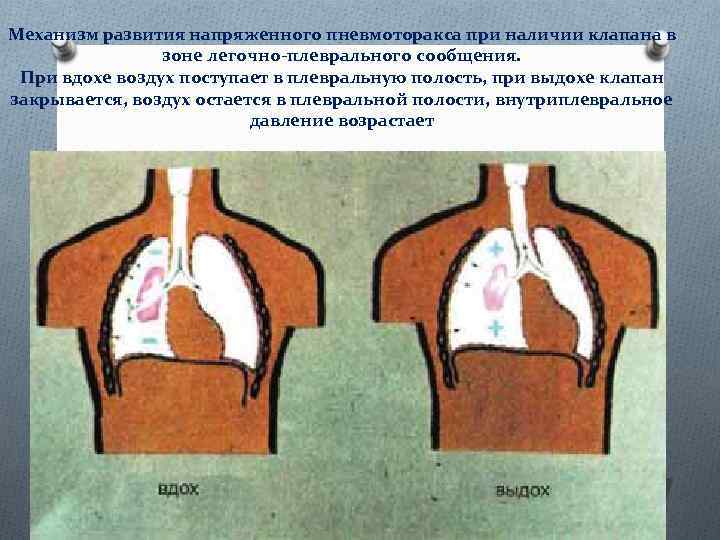

Схемы дыхания: Пневмоторакс на изображениях